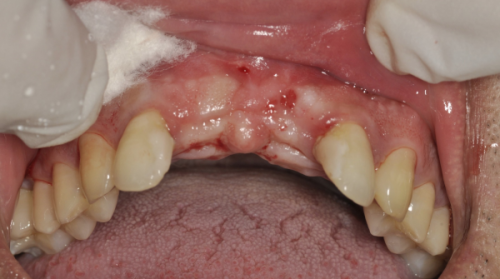

口腔种植的费用主要由种植体、牙冠和医疗服务这三个部分组成。其中,医疗服务部分在种植牙整体费用中所占的比重相对较高。近期国内范围内的登记调查初步结果显示,以各省份国有医疗机构单颗常规种植为例,医疗服务部分的平均费用超过了6000元,有些省市甚至超过了9000元。这也是导致种牙费用居高不下的一个重要原因。过高的价格让特别多患者只能对种植牙望而却步,而现在政策的实施有望改变这一现状,实现种植牙价格大幅下降,让更多人能够负担得起种牙费用。